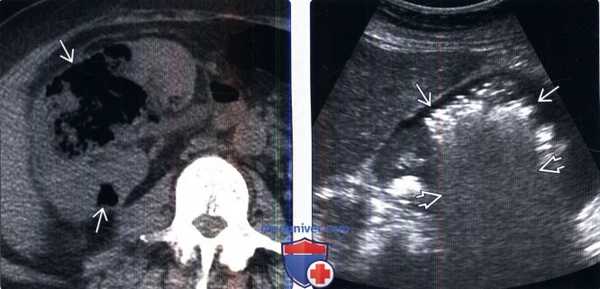

(Правый) На серошкальном УЗ срезе у другого пациента визуализируются множественные точечные гиперэхогенные скопления газа в субкапсулярном пространстве, сдавливающие нижний полюс правой почки. Эти гиперэхогенные очаги не фиксированы (движутся в жидкости) и свободно перемещаются при исследовании в реальном времени. (Левый) На УЗ срезе с цветовой допплерографией у этого же пациента визуализируется цветовой сигнал в виде артефакта мерцания, обусловленного пузырьками газа. С целью исключения истинного кровотока исследуется спектр допплеровской волны. В этом случае волна представляет из себя шум (не показано), говорящий о том, что данная цветовая область является артефактом, а не истинным кровотоком.

(Правый) На обзорном аксиальном КТ срезе у того же пациента подтверждены множественные скопления газа в субкапсулярном пространстве, приводящие к сдавливанию почки. (Левый) При КТ с контрастированием визуализируется значительно увеличенная правая почка с отсроченным контрастированием на нефрограмме по сравнению с неизмененной противоположной почкой. Множественные скопления газа в верхнем полюсе паренхимы подтверждают диагноз эмфизематозного пиелонефрита.

(Слева) КТ без контрастирования, аксиальная проекция: большое скопление газа В в правой почке. Этот признак характерен для эмфизематозного пиелонефрита. Скопления жидкости нет. КТ-метод выбора для постановки диагноза и оценки распространения газа.

(Справа) УЗИ правой почки в сагиттальной плоскости: у этого же пациента визуализируются эхо-сигналы в паренхиме почки, ассоциированные с «грубой акустической тенью».